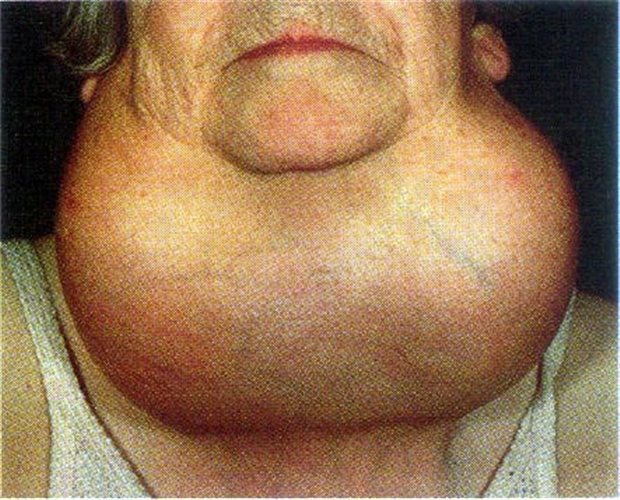

巨大甲狀腺癌